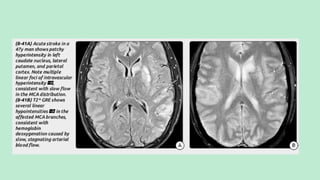

MULTIPLE EMBOLIC INFARCTS

The differentials of multiple embolic infarcts are:

1. Cardio-embolic infarcts.

2. Fat embolism.

3. Gas embolism.

CARDIAC AND ATHEROMATOUS EMBOLI

Hallmark: Small acute infarct in

multiple different vascular

distributions.

Peripheral signs: Splinter hemorrhage

Echo:Valvular vegetations, intra cardiac

filling defects

Tend to involve terminal cortical branches

CT SCAN

In contrast to large artery territorial strokes, embolic

infarcts tend to involve terminal cortical branches. The

GM-WM interface is most commonly affected.

NECT: Low-attenuation foci, often in a wedge-shaped

distribution.

Atherosclerotic emboli occasionally demonstrate

calcification. Septic emboli are often hemorrhagic.

CECT scans: May demonstrate multiple punctate or

ring-enhancing lesions.

MRI

MRI: Multifocal peripheralT2/FLAIR hyperintensities. Hemorrhagic emboli

cause "blooming" onT2* sequences (most sensitive sequence: DWI).

Typical finding in multiple emboli infarcts: Small peripheral foci of

diffusion restriction in several different vascular distributions.

T1 C+ imaging may show multiple punctate enhancing foci.

Septic emboli often demonstrate ring enhancement, resembling